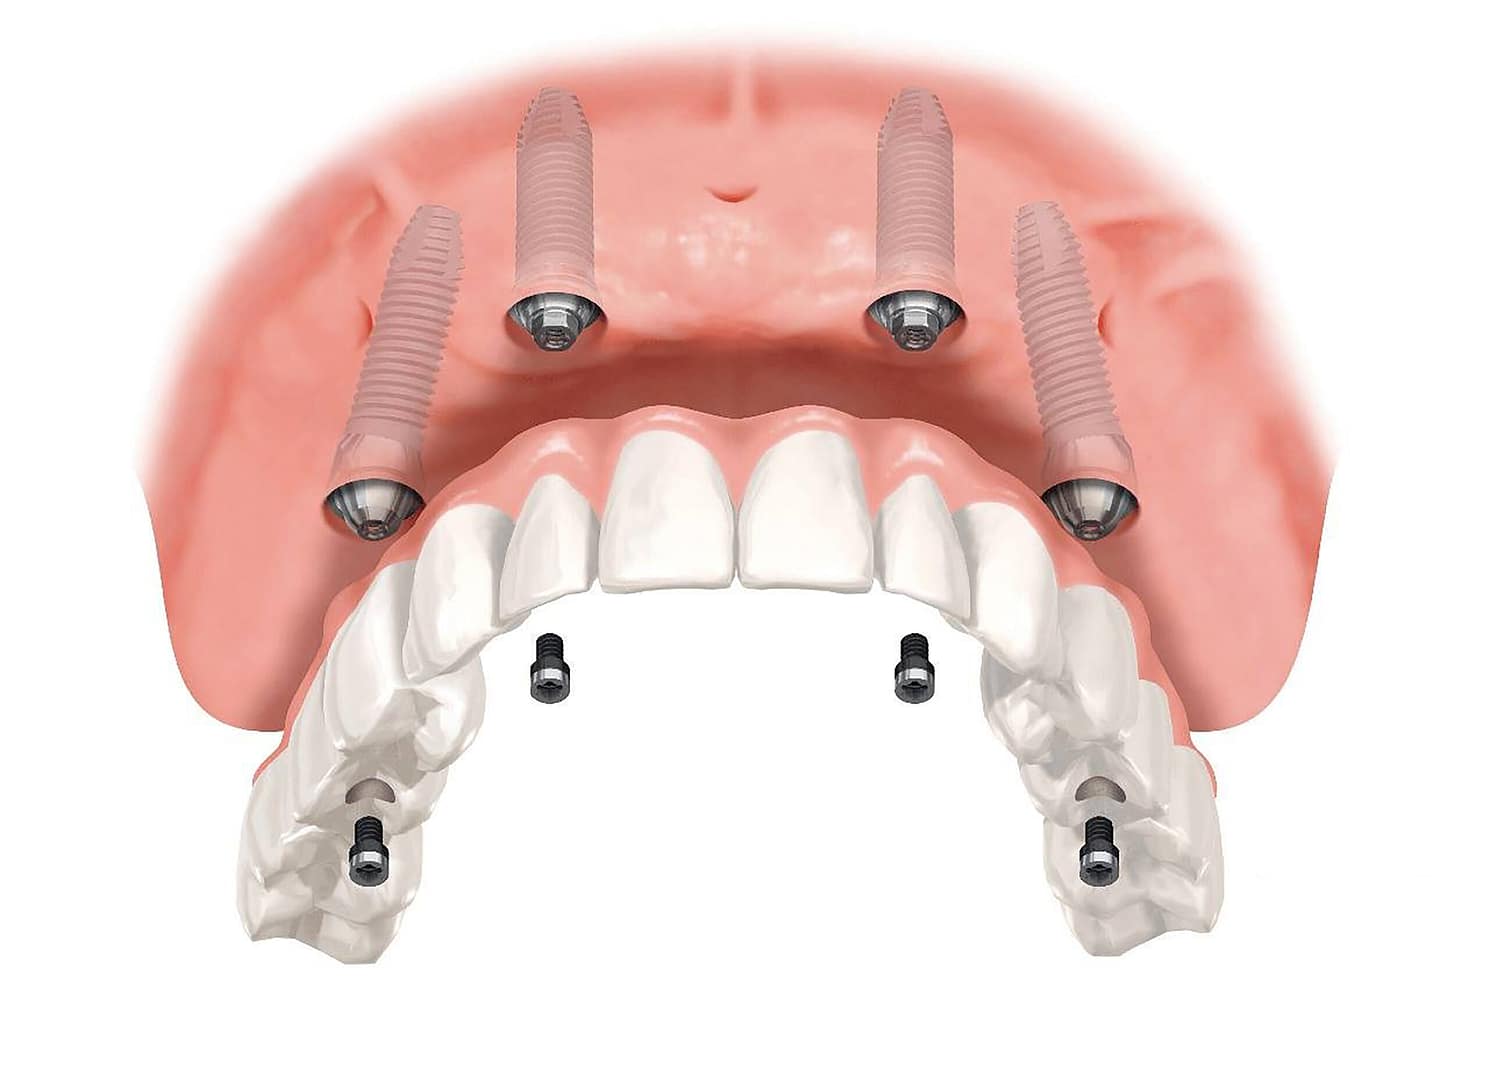

El All-on-4 (Todo sobre Cuatro) es un concepto quirúrgico y protésico desarrollado y patentado por el Dr. Paulo Maló, que se basa en la colocación estratégica de solo cuatro implantes dentales para soportar una prótesis fija completa e inmediata. La genialidad del concepto radica en la posición de esos cuatro implantes:

- Implantes Anteriores: Se colocan dos implantes rectos en la parte frontal de la mandíbula o el maxilar.

- Implantes Posteriores: Se colocan dos implantes en la zona posterior, pero con una inclinación de hasta 45 grados.

3.- Carga Inmediata: La colocación inclinada y la distribución de los cuatro puntos de anclaje garantizan la estabilidad primaria necesaria para la Carga Inmediata (colocar la prótesis fija el mismo día).

Este es el beneficio más apreciado. Si el protocolo se cumple rigurosamente y los cuatro implantes logran la estabilidad primaria, usted recibe una prótesis provisional fija atornillada a sus implantes el día de la cirugía o al día siguiente. No tendrá que pasar tiempo usando una dentadura removible.